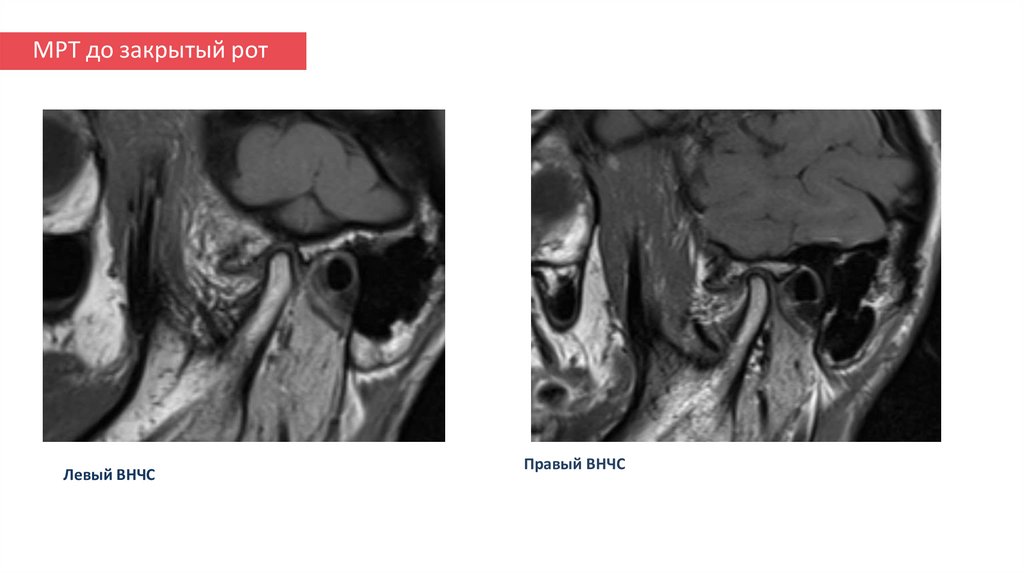

МРТ после закрытый рот

17. МРТ до закрытый рот

Левый ВНЧС

Правый ВНЧС